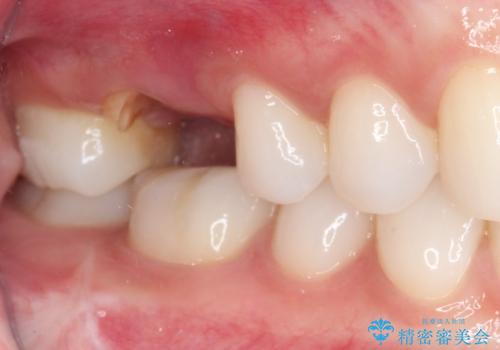

- 歯がほとんどなくなってしまうまで虫歯を放置してしまったとのことで来院された患者様です。

抜歯が必要であることは患者様自身も理解されており、インプラントによる欠損補綴治療を希望されていらっしゃいました。

抜歯前のCTにより、インプラントを埋入するために必要な歯槽骨量が不足することが予想されたため、サイナスソケットリフトにより上顎洞内の粘膜を挙上して、インプラントを埋入することとしました。

虫歯を放置した期間が長かったため、対合の下顎大臼歯が上顎に迫ってきており、咬み合わせは非常にシビアでした。

仮歯装着中に頻繁に脱離したため、オールセラミッククラウンは脱離の少ないスクリュータイプとしました。